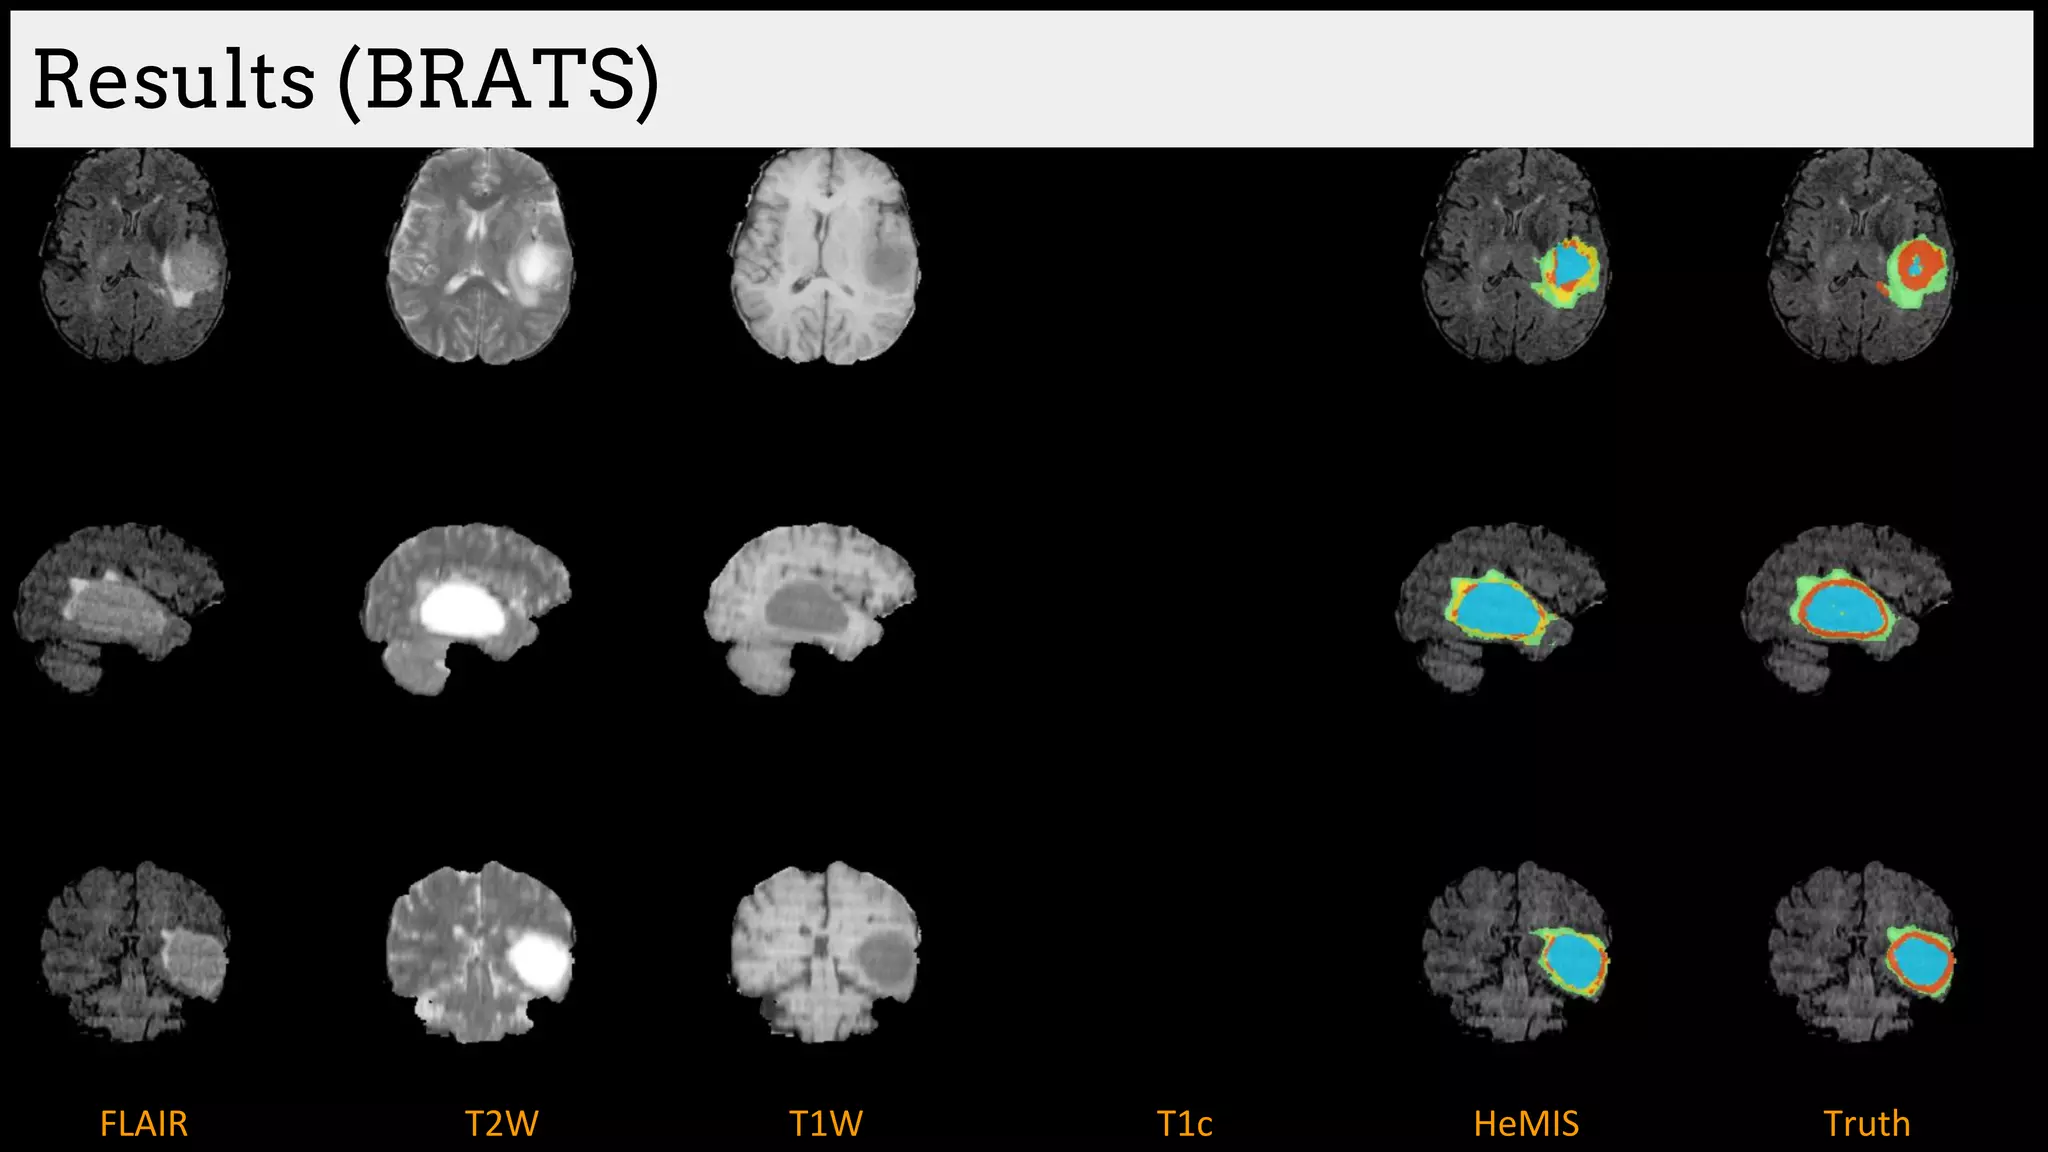

Results (BRATS)

Brain tumor segmentation (BRATS2013 dataset)

T1 T2

T1C Flair

GT

Edema

Necrosis

Non-enhanced

Enhanced

Training data:

220 subjects with high grade and

54 subjects with low grade tumors

Dice Similarity

[Havaei et al. HeMIS: Hetero-Modal Image Segmentation, MICCAI 2016]